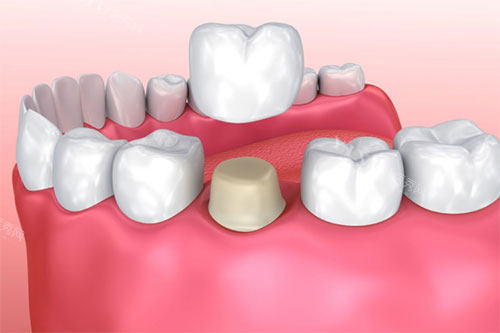

2. 牙冠的“生物学保护”:封闭根管口

根管治疗后,牙本质小管暴露,易滋生细菌导致再感染。牙冠通过以下方式封闭:

边缘密合:减少细菌侵入

抗微渗漏:防止唾液中的细菌进入根管

实例:一位未戴冠患者,3年后因根管再感染需重新治疗,而戴冠者5年内再感染率不足5%。

3. 牙冠的“美学修复”:修养牙齿形态

根管治疗后,牙体可能因龋坏或治疗需要磨除部分组织,导致:

颜色变暗:牙髓坏死后牙体脱水

形态异常:如“小尖牙”或“歪牙”

牙冠可定制与邻牙匹配的颜色和形态,修养自然美观。